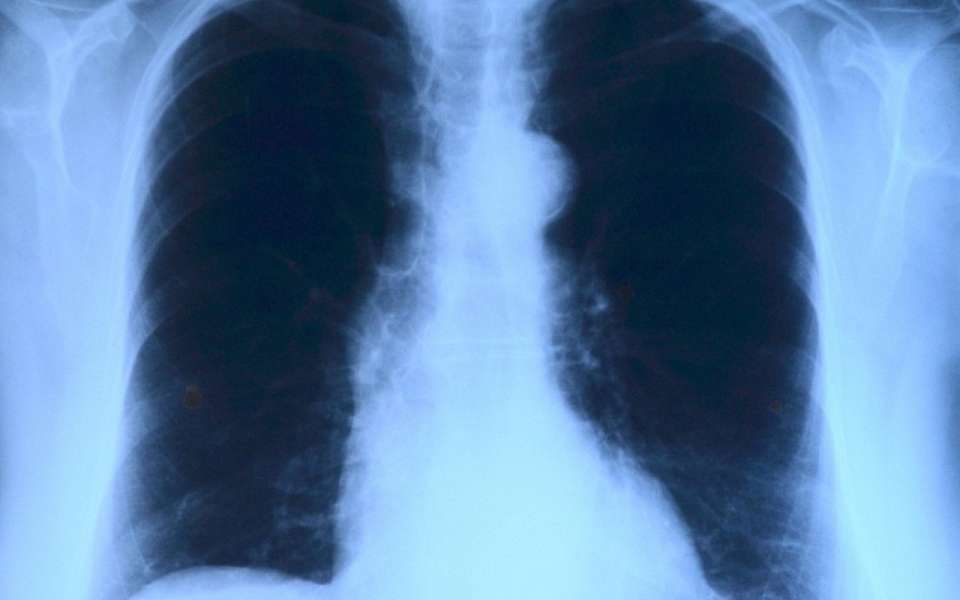

Оба этих гражданина состоят на учете в тубдиспансере, им показано стационарное лечение, но они всячески этого избегали. Тем самым ставя под угрозу здоровье и жизнь других местных жителей – ведь туберкулез заразен.

В итоге суд требования прокурора удовлетворил. Оба пациента пройдут принудительное обследование в областном тубдиспансере и там же должны пройти лечение. Исполнение этого решения ляжет на службу судебных приставов.